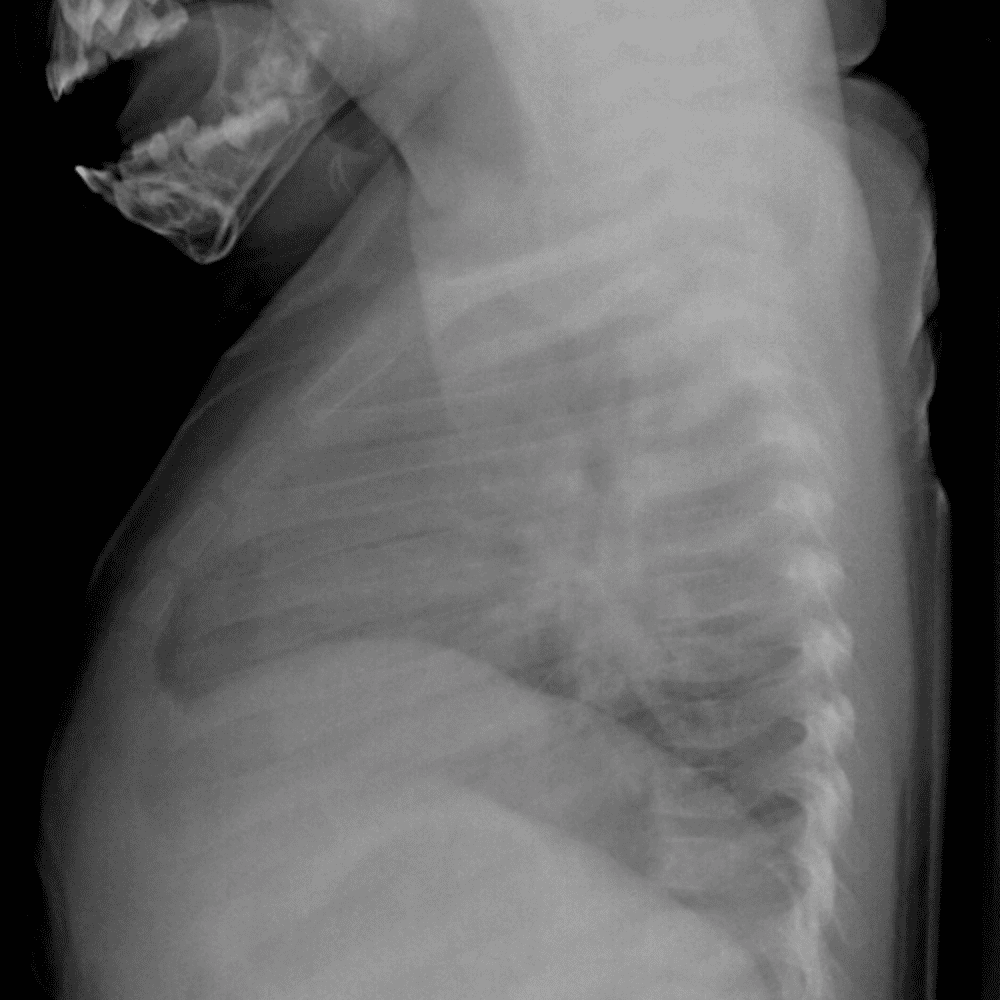

Peds Chest

Practice

Simulates call by including subtle or difficult cases and some normals.

50 cases